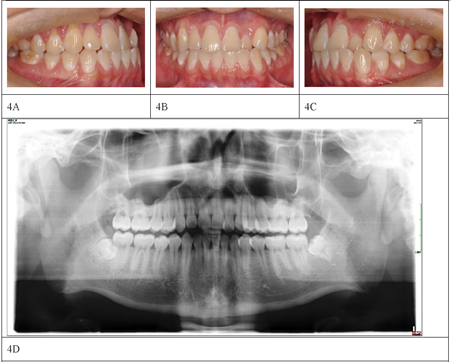

2014年8月再次就诊中山大学附属口腔医院正畸科,主诉为牙齿拥挤复发,患者自述未遵医嘱戴用保持器,现因牙齿拥挤复发要求矫治。临床检查可见上颌左侧侧切牙与对颌牙呈反

关系,上下牙列轻中度拥挤,磨牙关系为中性,右侧尖牙关系偏近中。全景片显示下颌第三磨牙阻生(图4)。2014年8月粘结全口直丝弓固定矫治器,上下颌前牙区配合邻面去釉获得间隙,逐步更换弓丝,上下颌采用0.019英寸×0.025英寸不锈钢丝作为稳定弓丝,配合颌间短Ⅲ类牵引维持前牙覆合覆盖及调整尖牙磨牙关系,保持3个月后拆除固定矫治器(图5),佩戴透明保持器。二次矫治治疗时长25个月(首次矫治结束后55个月),患者在二次治疗中已经拔除阻生的第三磨牙,侧切牙反

解除,拥挤解除,磨牙及尖牙关系均调整为中性。